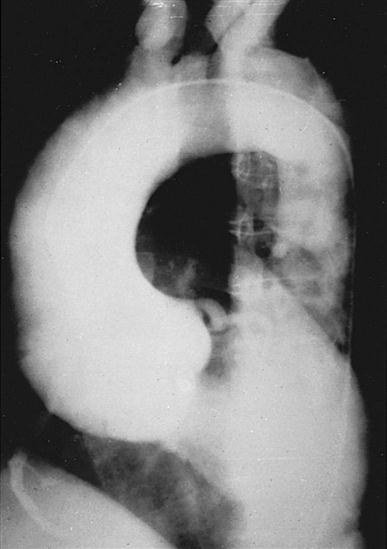

Chest radiography provides information about the size of the cardiac chambers, thoracic aorta, and pulmonary vasculature as well as the presence of calcium in valves, pericardium, coronary arteries, and aorta (Figure 25-8). Lateral chest radiographs of patients with prior sternal surgery show the chest wires and extent of pericardial adhesions. Magnetic resonance imaging (MRI) enables assessment of myocardial viability and also can image vascular structures with MRI angiograms that provide great clarity (Figure 25-9, A). In patients with suspected aortic or other vascular abnormalities, a computed tomography (CT) scan of the chest with intravenous injection of a contrast medium creates x-ray serial “slices” of the body area under study (see Figure 25-9, B). CT angiography is especially useful to image the aorta and the great vessels. CT images of the coronary arteries are used increasingly to identify areas of coronary calcification (shown in Figure 25-9, B), a recognized CV risk factor. One study demonstrated the value of coronary artery calcium scoring to identify patients who may be asymptomatic for CAD, but are at risk for increased mortality (Tota-Maharaj et al, 2012).

CT scans may be contraindicated in very unstable patients because their position in the tubelike scanner makes patient access difficult. Less frequently performed is arteriography with radiographic contrast dye to determine the size and location of the lesion and the site of the intimal tear in aortic dissections (Figure 25-10); digital subtraction angiography (DSA) provides clear images and requires less contrast material.